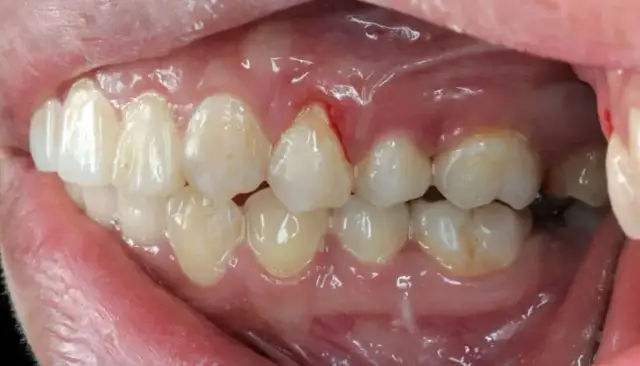

Recesja dziąseł: poznaj objawy, przyczyny i skuteczne metody leczenia. Dowiedz się, jak zapobiegać cofaniu dziąseł i chronić swój uśmiech.